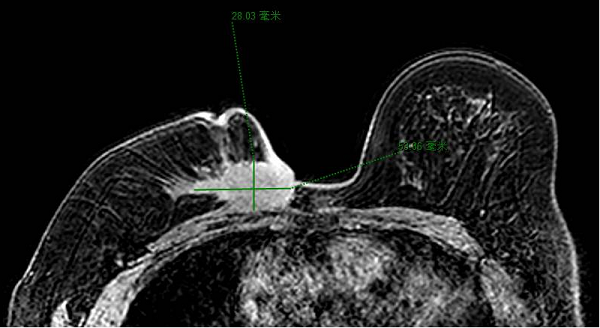

今年四月,命運(yùn)給陳女士開了一個(gè)殘酷的玩笑,她被確診為右乳腺癌伴腋窩淋巴結(jié)轉(zhuǎn)移。此時(shí)的她,乳房局部已出現(xiàn)破潰。經(jīng)過6期的針對(duì)性化療后,腫物雖稍有縮小,但雞蛋大的腫瘤與胸骨緊鄰的復(fù)雜病情,仍讓治療陷入兩難。

腫瘤緊緊緊貼著胸骨,就像頑固的“釘子戶”,傳統(tǒng)治療方法難以在這場“拆遷”中,兼顧去除病灶以及體表完整。因此,制定一個(gè)能平衡二者關(guān)系的周密治療方案,成為決策的關(guān)鍵。